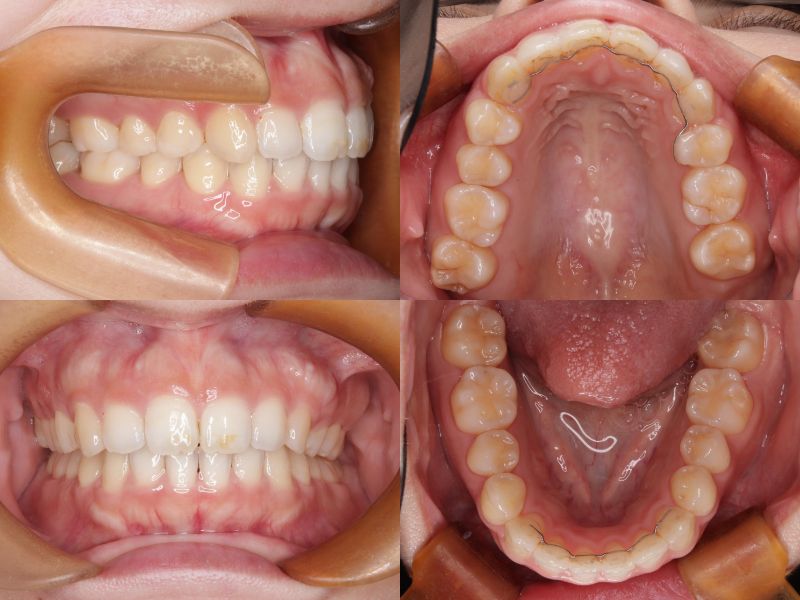

治療の結果、口元の突出感とディープバイトの改善が認められ、より自然で調和のとれた横顔を得ることができました。

治療期間:2年7ヵ月